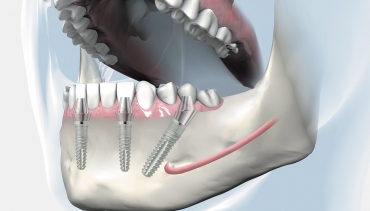

BREDENT Implantati

350 €